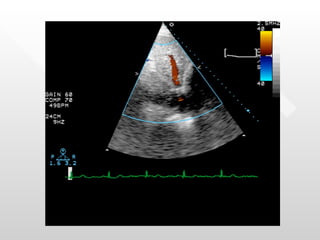

History of Present Illness 65 yo M with PMH of MV replacement in 1975 s/p Bjork Shiley mitral valve who presents to the cath lab with a two month history of decreased exercise tolerance.  Patient has a history of paroxysmal AF for the past ten years with multiple cardioversions.  Last cardioversion was in May, but his AF recurred and has persisted for the past two months. Previously, the patient was able to run 2.5 miles, but now he cannot run.  Patient underwent an exercise stress test in which he was only able complete stage II Bruce Protocol and had an echo which showed a normal EF, but the mitral valve was not able to be evaluated.

History of Present Illness As such, the patient was referred for cardiac cath in order to assess his coronary arteries and measure the gradient across the mitral valve.

History of PresentIllness 65 yo M with PMH of MV replacement in 1975 s/p Bjork Shiley mitral valve who presents to the cath lab with a two month history of decreased exercise tolerance. Patient has a history of paroxysmal AF for the past ten years with multiple cardioversions. Last cardioversion was in May, but his AF recurred and has persisted for the past two months. Previously, the patient was able to run 2.5 miles, but now he cannot run. Patient underwent an exercise stress test in which he was only able complete stage II Bruce Protocol and had an echo which showed a normal EF, but the mitral valve was not able to be evaluated.

History of PresentIllness As such, the patient was referred for cardiac cath in order to assess his coronary arteries and measure the gradient across the mitral valve.